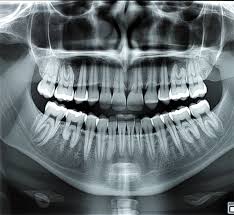

A dental x-ray is one of the most fundamental tools in modern dentistry, yet it is often misunderstood by patients. Unlike a visual exam, which only shows what’s happening on the surface, dental x-rays reveal hidden structures that determine whether a mouth is truly healthy—or quietly developing problems. This article from Luxe Smile Studio explains the role of dental x-rays from a diagnostic perspective, focusing on why they matter, what they uncover, and how they influence treatment decisions.

Even the healthiest-looking smile can conceal issues below the gumline or inside the tooth. A dental x-ray allows dentists to examine areas that are otherwise invisible, including:

- Tooth roots

- Jawbone structure

- Spaces between teeth

- Developing or unerupted teeth

- Areas beneath existing restorations

What Information a Dental X-Ray Actually Provides

A dental x-ray does more than confirm the presence of a cavity. It contributes to a broader diagnostic picture.

- Early tooth decay before it reaches the nerve

- Bone loss associated with gum disease

- Infections at the root tip

- Cracks or trauma not visible externally

- Alignment issues affecting bite and jaw balance